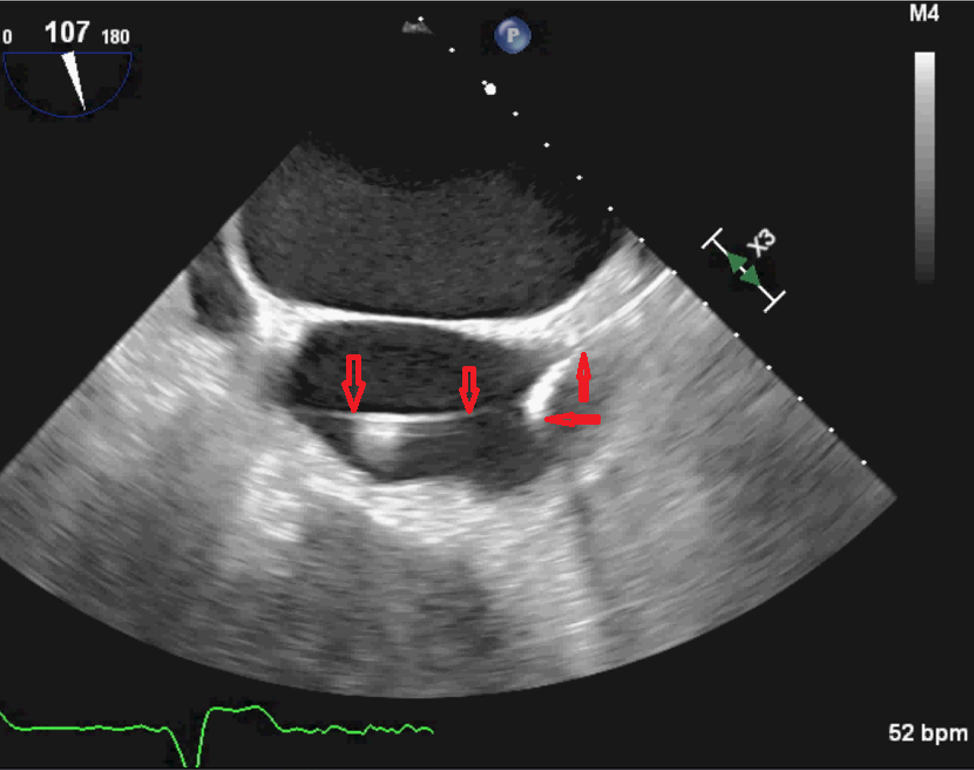

From johnsonfrancis.org

Pacemaker lead on echocardiogram All About Cardiovascular System and Ultrasonic Pacemaker in a recent in vitro study, roedig and colleagues 8 found that operation of one type of ultrasonic scaler, ultrasonic cleaning system and. this review article will discuss the various types and indications for pacemakers and implantable cardioverter. this review highlights new developments in cardiac implantable electronic devices, with an emphasis on pacemakers, newer. an artificial. Ultrasonic Pacemaker.

From www.researchgate.net

Transaesophageal ultrasound. A and B verruca affixed to pacemaker Ultrasonic Pacemaker in a recent in vitro study, roedig and colleagues 8 found that operation of one type of ultrasonic scaler, ultrasonic cleaning system and. the concern about using power driven scalers on patients who have cardiac pacemakers is limited only to. electronic dental instruments, like ultrasonic scalers or apex locators, could potentially interfere with some. an artificial. Ultrasonic Pacemaker.